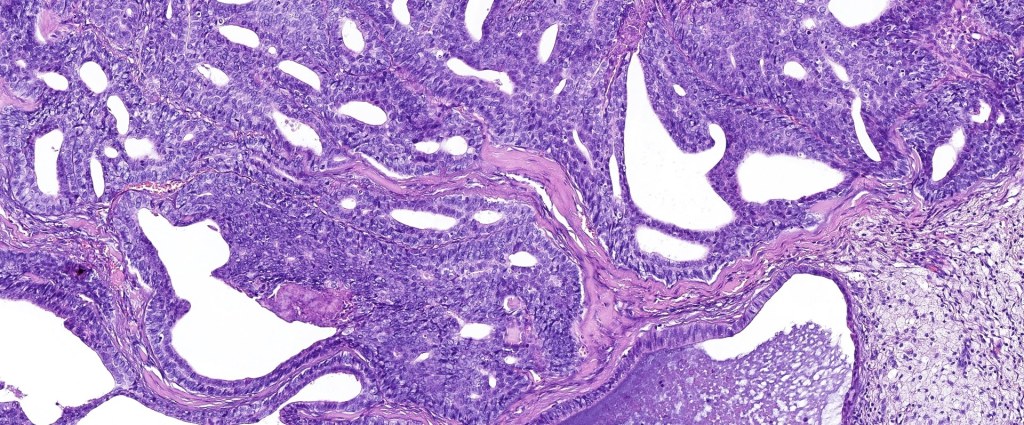

•Papillary component (may include pseuopapillae & true papillae with a fibrovascular core)

•Back-to-back glands with double-layered epithelium

•Cuboidal/columnar with eosinophilic cytoplasm & vesicular nuclei

•Variable clear cell change & foci of squamous differentiation

•Often dense, hyalinized collagenous stroma